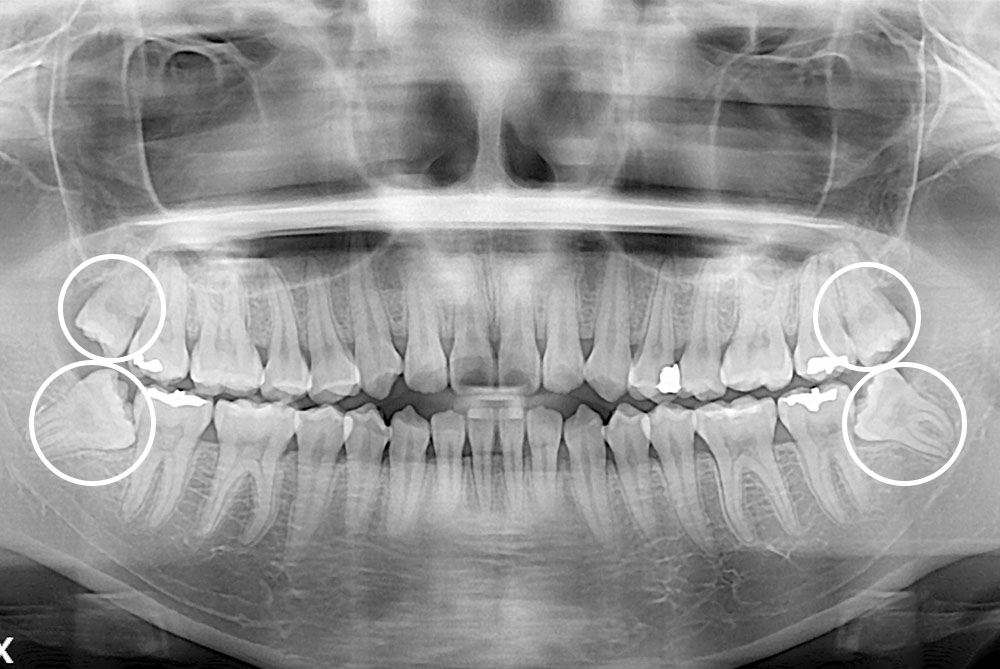

[사랑니] 매복 사랑니 발치

치료후 : 2018-10-04

세종치과는 구강악안면외과학 박사이신 원장님이 발치하는 치과입니다.